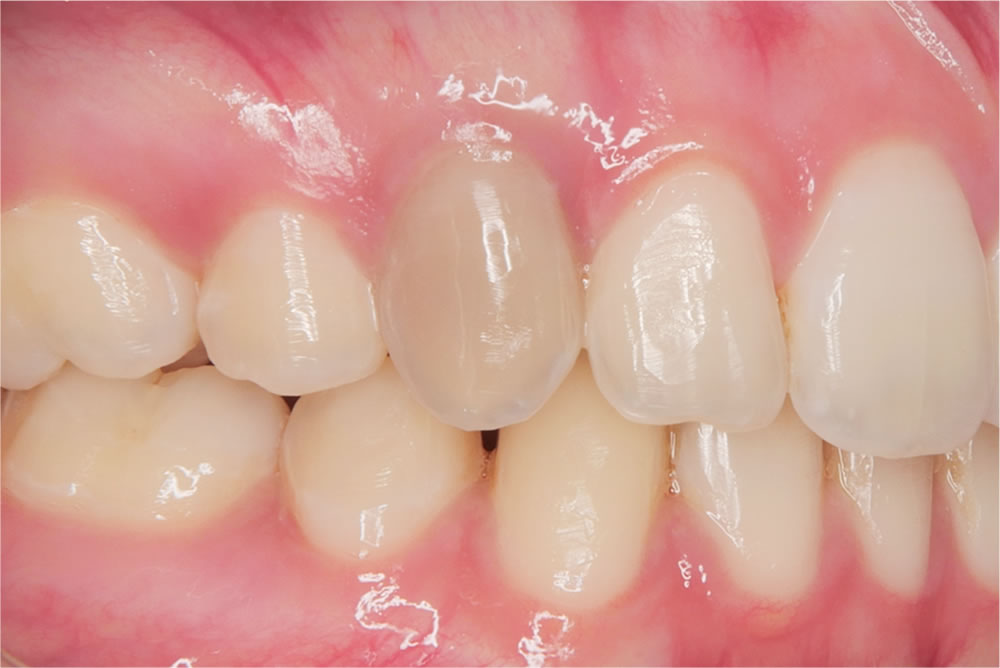

今回の患者さんも2回の薬剤の交換(約2ヵ月)の治療で歯の色が完全に回復し、自然で美しい白さを取り戻すことができました。患者さんからも「こんなに白く戻ると思わなかった」と非常に満足していただけました。

治療前後の比較

治療の総括

今回の患者さんは、治療後の結果に非常に満足していただけました。神経を失った歯は一般的に「予後が悪い」「長持ちしにくい」と言われています。

これにより、長期的に安定して使える歯へと回復できたと考えています。また、漂白処置により色調も自然で美しく改善し、患者さんにも「思った以上に綺麗になった」と喜んでいただけました。若い方への適切な治療選択肢を提示できたと感じています。